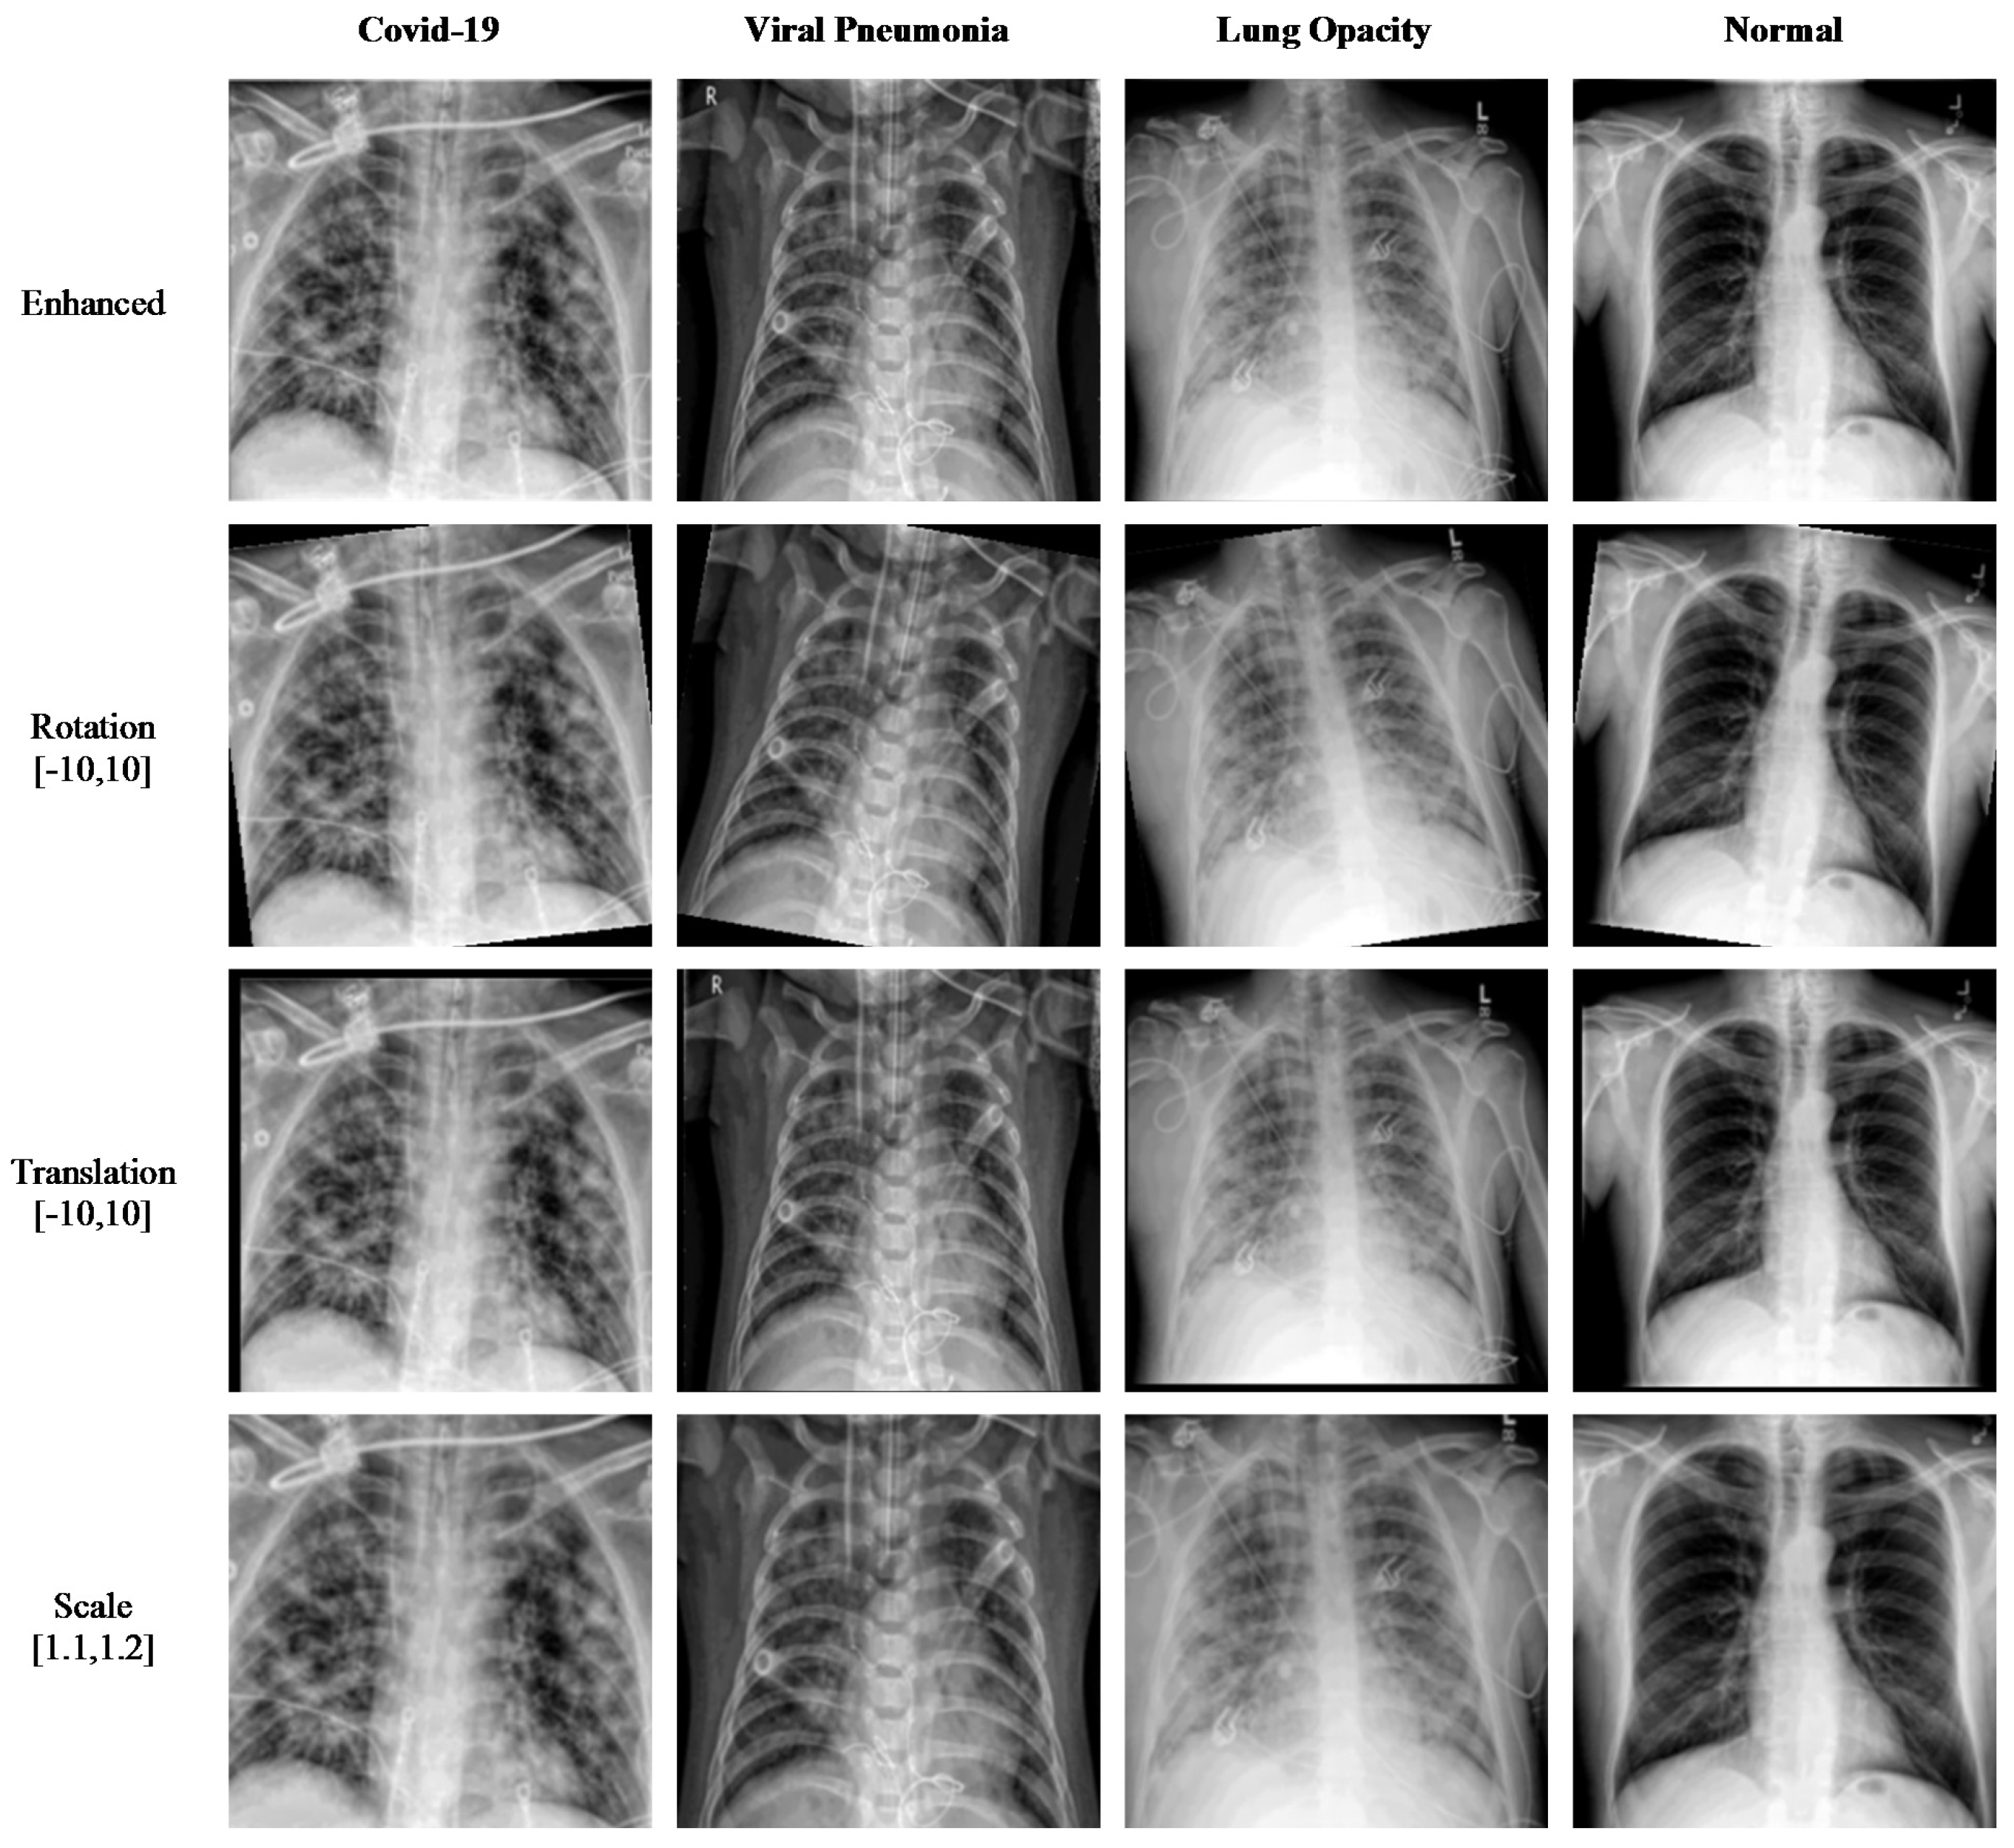

Figure 4 shows the results of applying the enhancement technique to the original images of four different types: COVID-19, viral pneumonia, lung opacity, and normal patients. The visual comparison between the original images and the enhanced images clearly shows that the images are smoothed and enhanced while keeping the strong edges intact.

Data augmentation is implemented on the images of the dataset to increase the size of the dataset. This is done through minor modifications to the existing images to produce synthetically modified images. Several augmentation techniques are used in this paper to increase the number of images. Rotation is one technique where images are rotated clockwise or counterclockwise to generate images with different rotation angles. Translation is another technique where basically the image is moved along the x- or y-axis to generate augmented images. Scale-out and scale-in is another approach, where basically a zoom in or zoom out process is done to produce new images. However, the augmented image might be larger in size than the original image, and thus, the final image is cut to size so as to match the original image size. Using all these augmentation techniques, the dataset size is increased to a size suitable for DL algorithms. In our research, the enhanced dataset (shown in

Figure 5) of COVID-19, Pneumonia, Lung Opacity, and Normal images is achieved with three different position augmentation operations: (a) X-ray images are rotated by −10 to 10 degrees; (b) X-ray images are translated by −10 to 10; (c) X-ray images are scaled by 110% to 120% of the original image height/width.